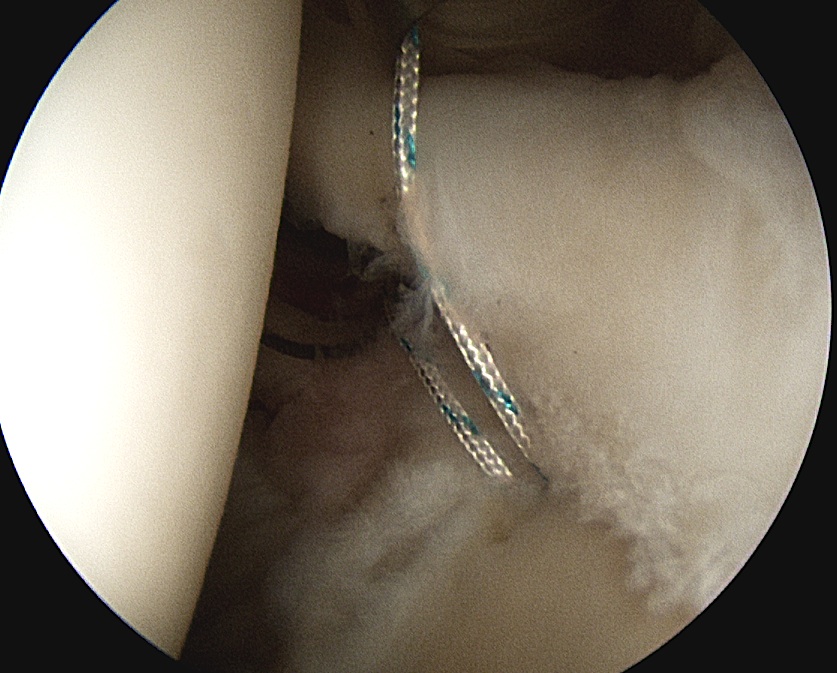

Anterior anchor

- best to pass the suture passer above the biceps to get good bite

- retrieve sutures and tie from port of Wilmington

Posterior 2 anchors

- pass suture passer under biceps